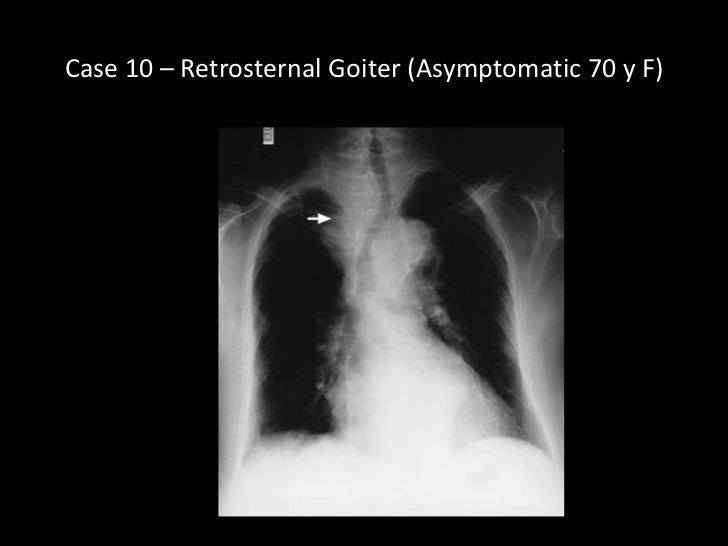

Goiters and Varieties » Internal goiter (plunging goiter, retrosternal

Chest X Ray For Goitre . Substernal goiters can remain asymptomatic for many years. A diagnostic assessment usually includes an evaluation of thyroid function, chest radiography, and computed tomography. A substernal goiter is a condition where there is an abnormal enlargement of your thyroid gland that extends into the chest. Consequently, incidental discovery of these goiters is not. Goiter is considered mediastinal if the lower pole of thyroid is not palpable with the neck in hyperextended position. There are many reported definitions of the. An additional diagnosis included neck/chest computed. Chest radiograph sgs are mostly diagnosed by deviation or narrowing of the trachea on posteroanterior chest radiographs.

Chest radiograph sgs are mostly diagnosed by deviation or narrowing of the trachea on posteroanterior chest radiographs. A substernal goiter is a condition where there is an abnormal enlargement of your thyroid gland that extends into the chest. Substernal goiters can remain asymptomatic for many years. Goiter is considered mediastinal if the lower pole of thyroid is not palpable with the neck in hyperextended position. A diagnostic assessment usually includes an evaluation of thyroid function, chest radiography, and computed tomography. Consequently, incidental discovery of these goiters is not. There are many reported definitions of the. An additional diagnosis included neck/chest computed.